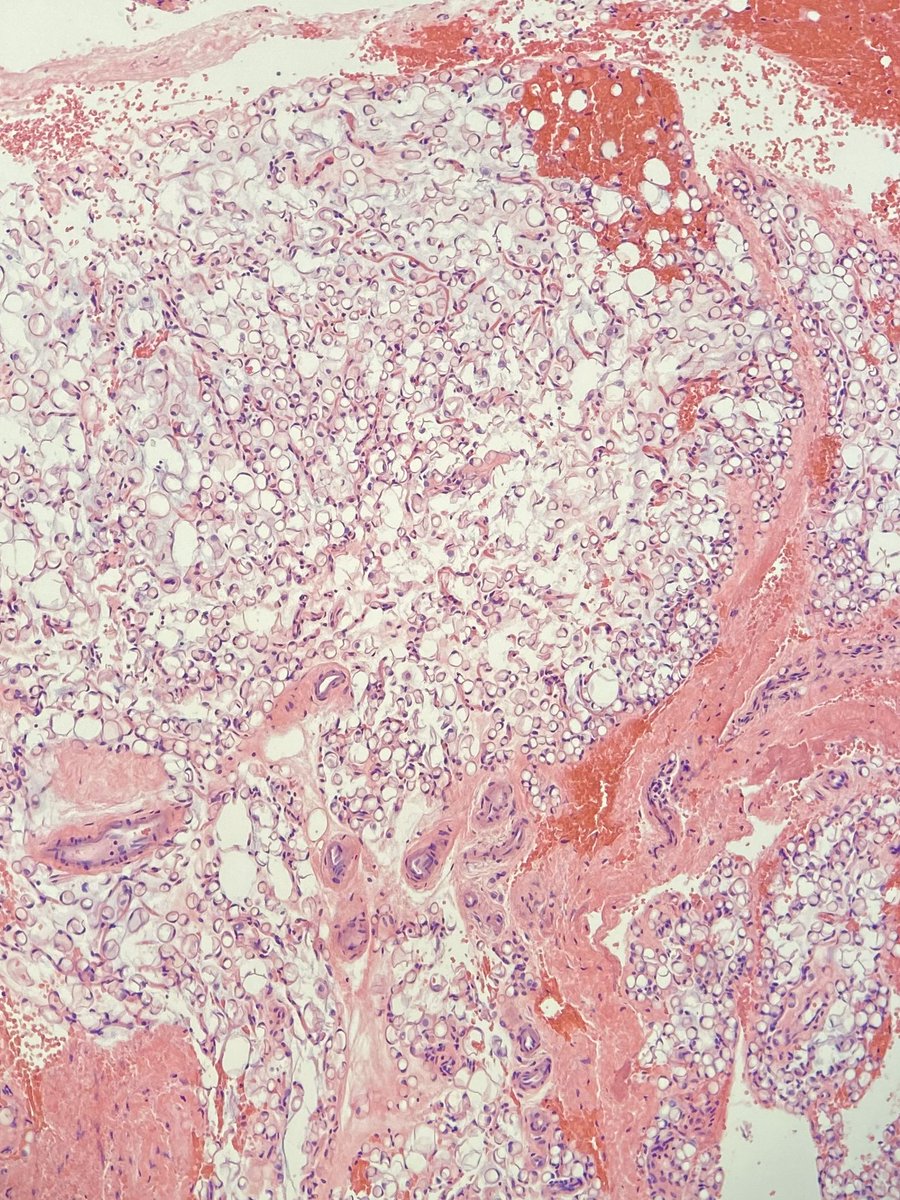

Epithelioid Angiomyolipoma in

#kidney. They have potential for aggressive clinical course. I do a risk stratification factoring in necrosis, atypia, and mitotic activity.#GUpath#Pathology#kidneycancer pic.twitter.com/9Y96lAfqfV